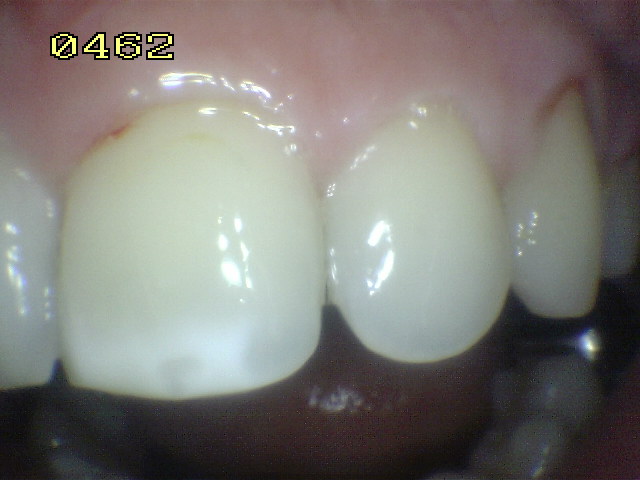

Una mancha oscura de dentina que se observa a través del esmalte intacto,  adyacente a la fosa y reborde marginal,  indica la presencia de desmineralización. (Imagen 0229)